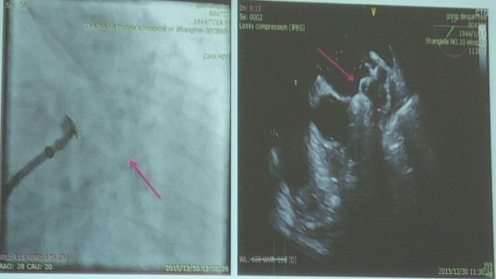

左心耳封堵术的过程

左心耳完成后的情形